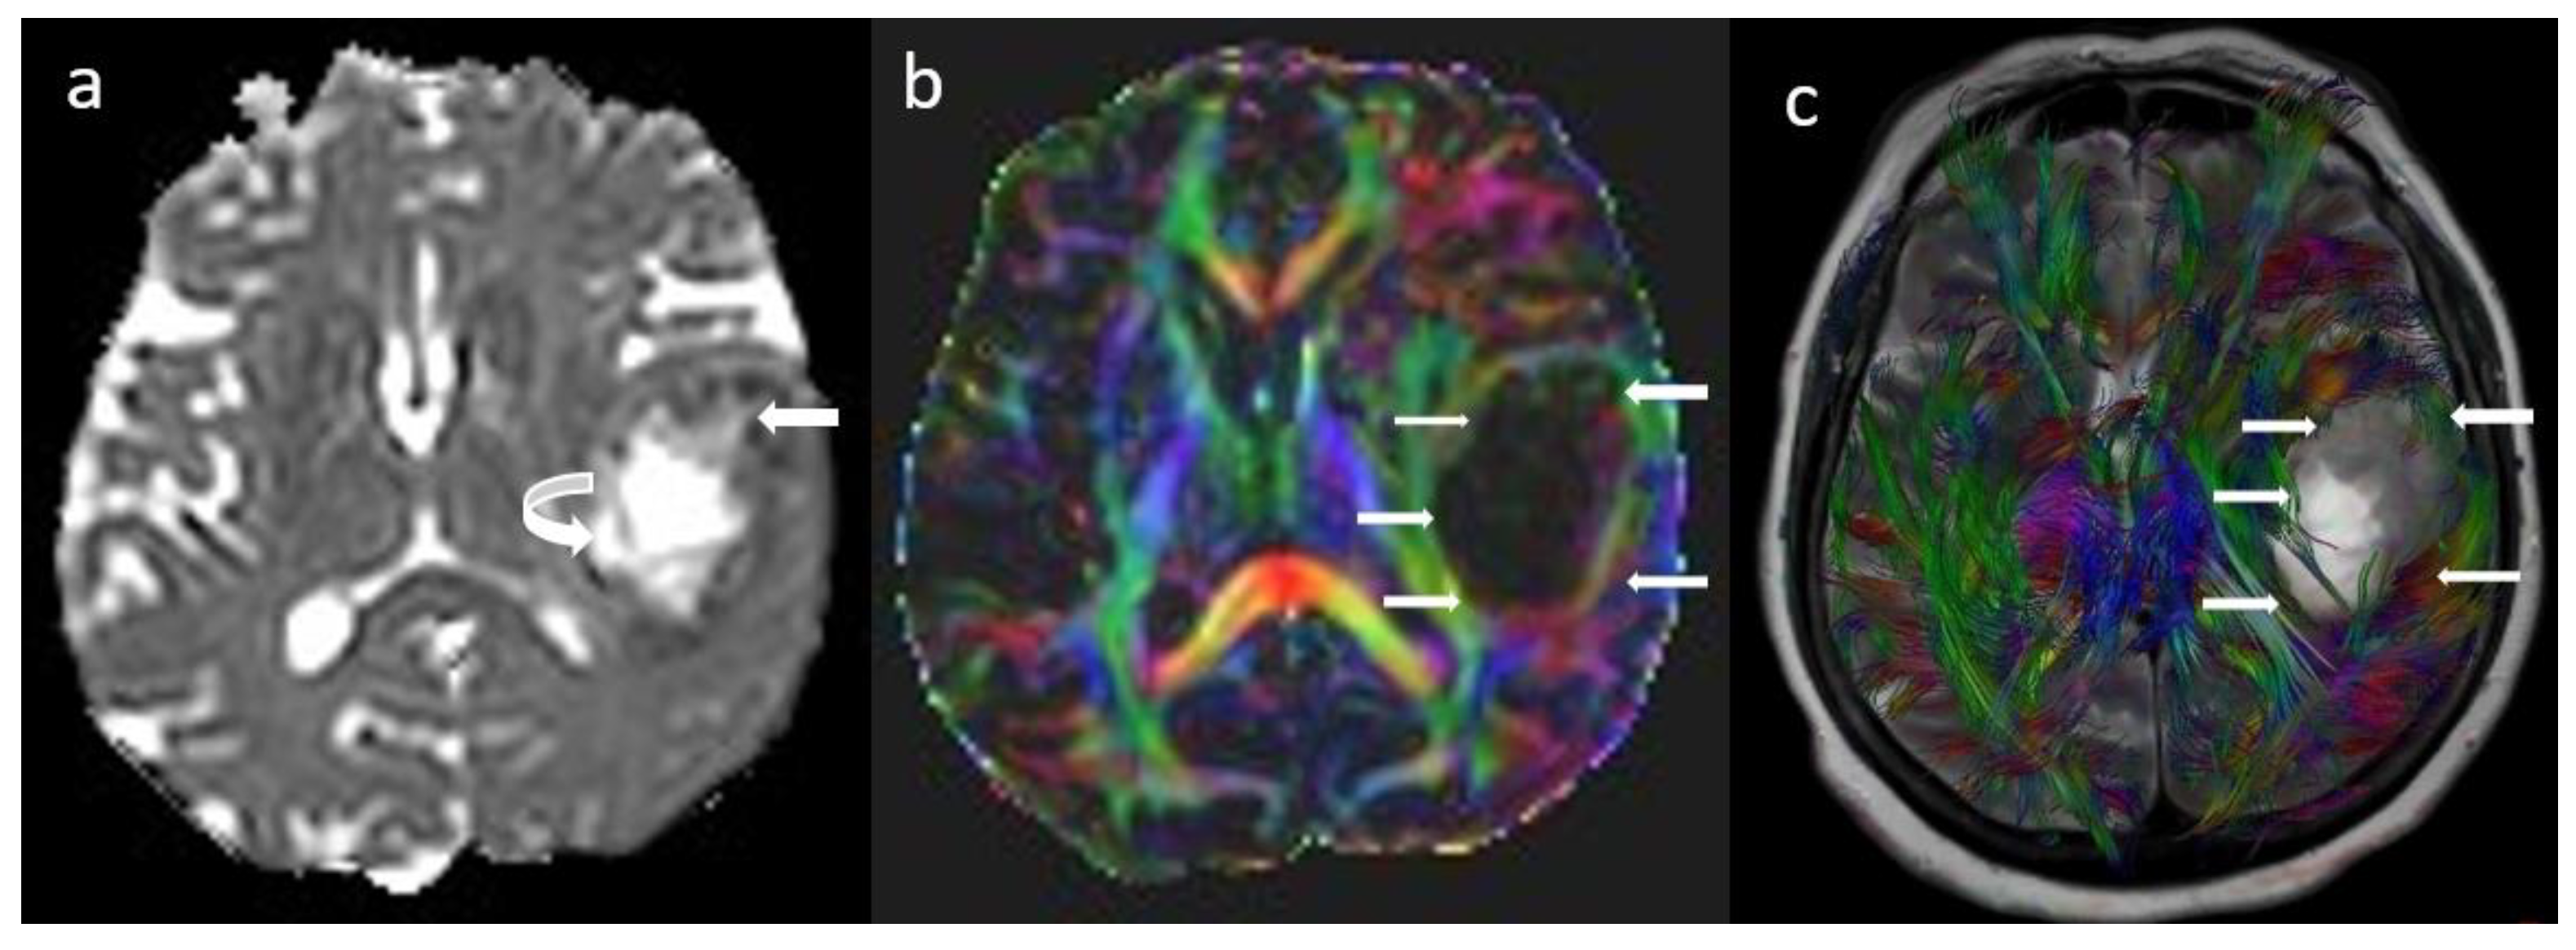

2.2. Diffusion-Weighted and Diffusion Tensor Imaging

4. Tumor Infiltration